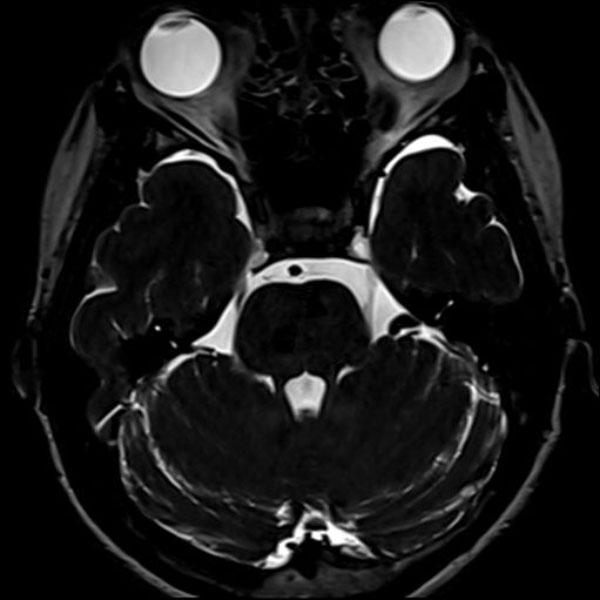

症例 '26年2月

No.

579

大阪府の病院

'26年2月

40代

右三叉神経痛

(顔面の痛みをとること)

手術前

減圧前

減圧後

術後血管撮影